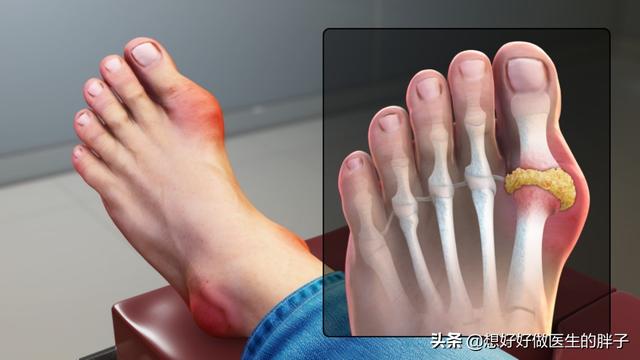

Comme cela a déjà été dit.La goutte provoque des rougeurs, des gonflements, de la chaleur et des douleurs très typiques chez le patient.Lors de la première crise, la goutte a tendance à se situer plus souvent dans la région des orteils, mais ce n'est pas absolu, la goutte qui se manifeste dans les coudes, les genoux, les doigts, ainsi que les poignets est de plus en plus fréquente.

La détermination de la goutte dépend principalement des articulations. Au début de l'apparition de la goutte, 53 % à 70 % des patients ont les articulations du premier orteil (appelées goutte du pied) rouges, gonflées, chaudes et douloureuses, généralement multiples, certaines pouvant aussi se manifester sous forme d'articulations multiples. Elle est fixe et asymétrique, et peut progressivement envahir des articulations plus importantes telles que les chevilles, les genoux, les poignets et les coudes.

Le premier symptôme est souvent une douleur articulaire qui se manifeste principalement au niveau des pieds, en particulier du gros orteil.

En outre, cetteL'articulation du gros orteil est également l'articulation la plus vulnérable aux traumatismes.L'acide urique peut se déposer dans les articulations à la suite d'un accident ou d'un traumatisme mineur, ce qui favorise le dépôt de cristaux d'acide urique.Bien entendu, la douleur articulaire provoquée par la goutte n'est pas limitée à cet endroit, comme le dos du pied, la cheville, le genou, etc. sont des parties communes, et il n'y a généralement pas de symétrie, et la douleur localisée en touchant le pied présente une rougeur, un gonflement et une chaleur, en plus de la chaleur de la peau au toucher.

Les orteils, la zone où les urates ont tendance à s'accumuler, et lorsque la goutte frappe, la douleur, littéralement, est atroce.

Lors d'une crise aiguë de goutte, on observe souvent une rougeur, un gonflement, une chaleur, une douleur et un dysfonctionnement localisés importants dans les articulations touchées (le plus souvent le gros orteil et le dos du pied).

Une crise de goutte peut se manifester par un jour de gonflement soudain et une douleur intense dans une articulation telle que le gros orteil (première articulation métatarso-phalangienne) du pied. Comme je l'ai dit au début, la goutte aiguë doit être précédée par la présence d'une hyperuricémie chez le patient, et si l'hyperuricémie est ignorée, elle peut évoluer vers la goutte avec des douleurs sévères.

De toutes les articulations, la zone la plus susceptible d'être touchée par la goutte est la première articulation métatarso-phalangienne. C'est là qu'environ 70 % des personnes souffrant de goutte auront leur première crise.

- Les symptômes de la goutte aiguë, outre la douleur, comprennent généralement une rougeur, un gonflement et une chaleur localisée à l'endroit de la crise, ainsi qu'une importante douleur à la pression. Une crise de goutte aiguë dans la première articulation métatarso-phalangienne peut entraîner l'impossibilité de porter des chaussures parce que le pied est enflé et que la douleur est si forte qu'il est impossible de marcher.